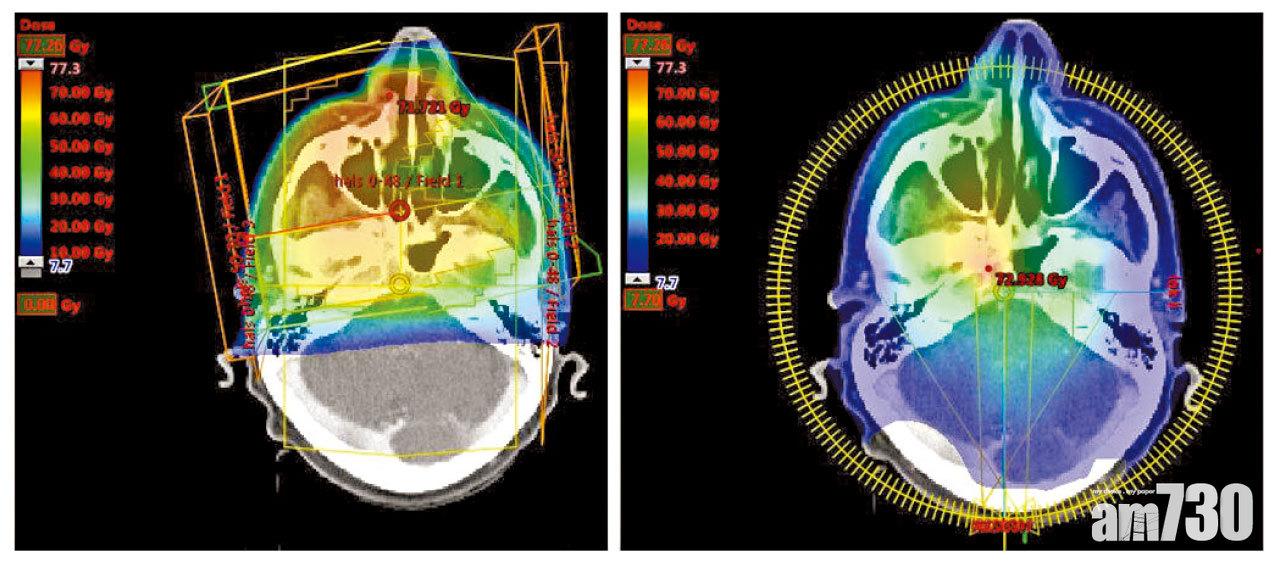

由於鼻咽癌位於頭部深處,而且附近有很多重要的組織,如腦幹、內頸動脈等,不宜做手術,因此放射治療(俗稱電療)是鼻咽癌的主要治療方案。吳雲英表示,傳統2D電療帶來的短期副作用和長期後遺症較多,包括味覺改變、難以吞嚥固體食物、口腔黏膜發炎甚至潰瘍、聽力下降、頸部組織硬化等,令日後病人的生活水平大打折扣。然而,隨著科技進步,電療已演變至3D立體調控放射治療(IMRT),由醫生界定腫瘤及須迴避的重要器官之範圍及劑量,然後利用電腦程式計算出最佳的入射角度和強度,盡量把射線集中在腫瘤位置,減低周邊重要組織的劑量。透過此技術,腫瘤可接收更高的放射劑量,從而提升治愈率。同時,周邊組織如口水腺接收的放射劑量則可減低,減少產生副作用。

IMRT能夠把射線集中在腫瘤位置,減低周邊重要組織的劑量。